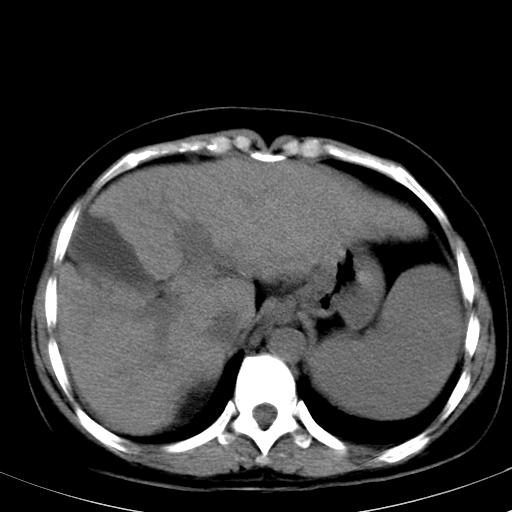

标题: CT19818:女40,脾大伴贫血,无肝炎病史 [打印本页]

标题: CT19818:女40,脾大伴贫血,无肝炎病史

血常规血红蛋白102,

骨穿,诊断再障,无其他病史

肝各叶比例失调,肝裂增宽,支持肝硬化\\脾大.

肝硬化、门脉高压、脾大。再障+肝硬化促成巨脾。

肝叶比例失调,肝左叶明显增大,包膜欠规整,脾大,支持考虑肝硬化、门脉高压、脾大。